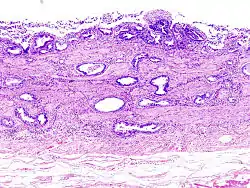

معظم هذه السرطانات من النوع الغدي إلا أن بعضها يكون سرطانة خلايا حرشفية، عادة ما يهاجم السرطان أعضاء الكبد والمعدة والبنكرياس والإثني عشر.